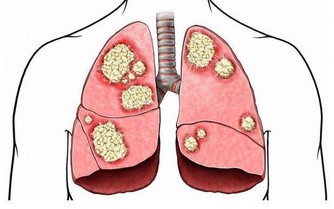

吃飯經常有4個症狀,當心胃癌敲門

只佔一個也別忽視

想要胃好好的,除了要改掉上述的惡習,還要及時發現胃的“委屈”,緩解胃的“傷害”,否則等到胃癌來敲門,就晚了。

如果你經常出現下面幾種情況,最好考慮做一下胃鏡檢查。

1. 反复腹痛,尤其是上腹部脹痛不適

上腹部脹痛不適、噯氣、食慾不振、消化不良、進食後異常飽脹,甚至在吃了少量食物後,也莫名的飽,這些是早期胃癌最常見的症狀。

2. 貧血、大便發黑

胃癌可導致胃部出血,因此人會出現貧血、便血、大便發黑的症狀。

3.有明顯的消化道症狀,如經常嘔吐、厭食、反酸、噯氣、上腹飽脹等。

胃癌會減弱胃的蠕動功能,造成進食後胃酸可能隨著食物反流回食道,引起燒心、反酸。

4. 短期內暴瘦

胃里長有腫瘤,不僅會影響食慾和正常進食,還會導致食物分解不當,影響吸收。

如果短期內暴瘦,比如一個月就減了10斤,不要因為減了些肉而高興,要當心是否被胃癌或其他惡性腫瘤盯上。